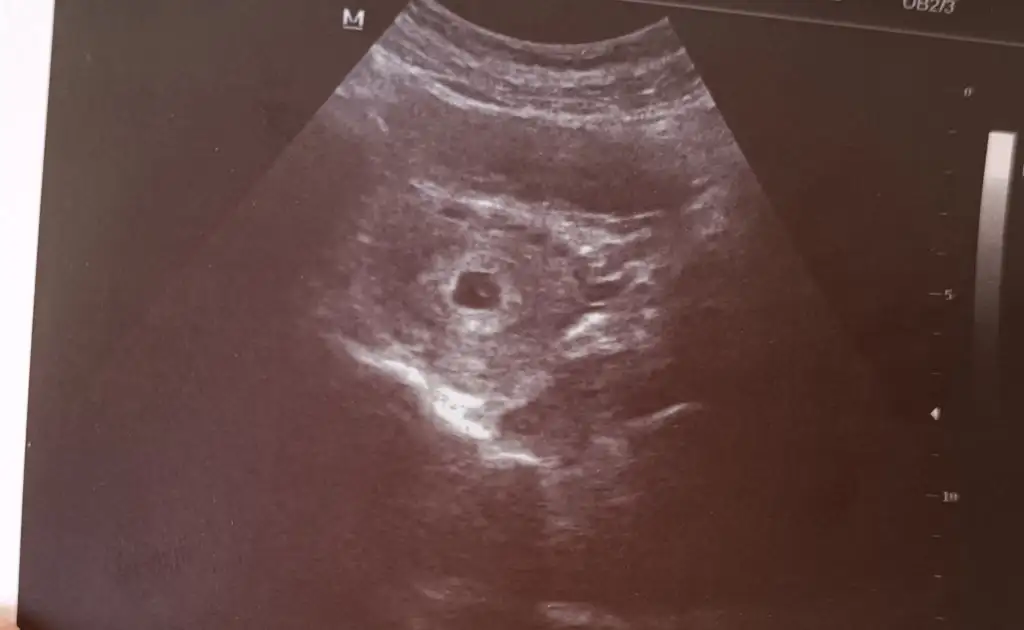

Ooyyy maşallahÇok şükür benim de kesem düzelmiş doktor hiç korkma çok güzel, yolk kesesi de oluşmuş kalbi de oluşmuştur ama şimdi dinlemeyelim dedi![]()

Canim benim geç döllenme olduğu için kaç haftalık olduğunu söylemedi doktor ona çok moralim bozuldu. Normal adet tarihime göre 7 haftalık çıkıyor ama geç döllenme işteMasallah Allah sağlıkla kucağınıza alabilmeyi nasip etsin kac günlükte gorundu kese bende 4+6 da gidicem de doktora acaba kese görünür mu

normalde ben eminim bugün de kalp atışı duyulurdu ama ben eski doktoruma geldim cihazı çok çok eski normalde kalp atışı için bile 9. Haftada çağırıyor düşün yani